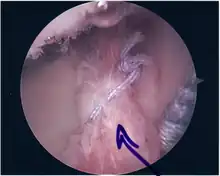

Repair of SLAP Tear

• The glenoid and labrum are roughened to increase contact surface area and promote re-growth.

• Locations for the bone anchors are selected based on number and severity of tear. A severe tear involving both SLAP and Bankart lesions may require seven anchors. Simple tears may only require one.

• The glenoid is drilled for the anchor implantation.

• Anchors are inserted in the glenoid.

• The suture component of the implant is tied through the labrum and knotted such that the labrum is in tight contact with the glenoid surface.